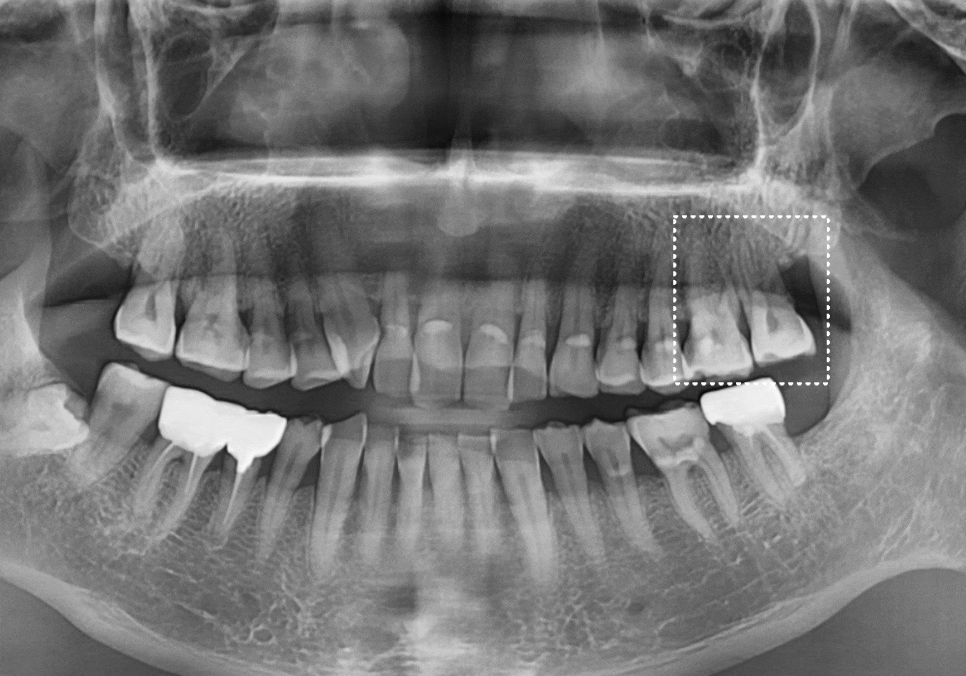

왼쪽 위 어금니 두 개(#26, #27)가 동시에

시큰거려서 내원하셨는데요~

정밀 CT를 통해 분석해 보니,

치아에 금이 가 있는게 보입니다.

앞쪽 어금니(#26)

: 금이 머리 쪽에만 머무른

'치관 파절'로 예후가 좋아 보였지만,

맨 끝 어금니(#27)

: 금이 뿌리 쪽으로 깊게 내려간

'수직 치근 파절' 상태였습니다.